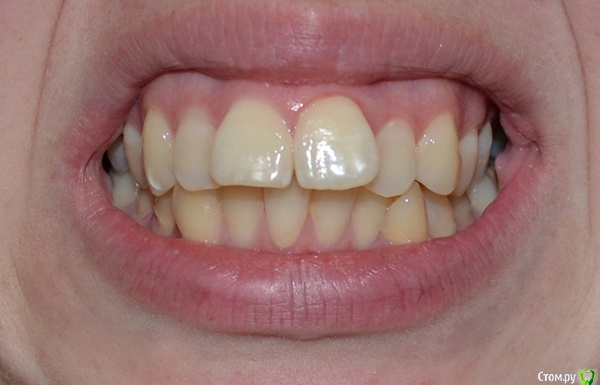

Мне 22 года, планирую исправить проблемы с прикусом, сейчас ищу информацию, рассматриваю варианты.

Очень нужен совет - действительно ли в моем случае лучшим выбором будет удаление 4ок на обеих челюстях?

А я никак не могу решиться. Особенно почитав этот форум, где у многих людей после удаления возникают проблемы с эстетикой лица и суставами. Кроме того, я боюсь, что без четверок на ВЧ зубы провалятся слишком далеко назад. Да, передние резцы сравняются с остальными, но мне бы не хотелось, чтобы все челюсти в общем, а за ними и губы сильно сдвинулись "вглубь", это еще больше испортит лицо.

В общем, прилагаю фото, подскажите, пожалуйста, что можно с этим сделать.